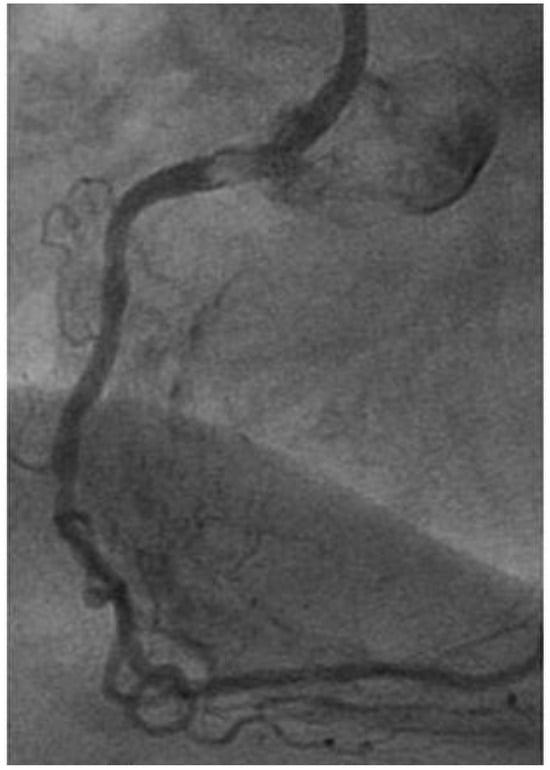

A patient with Morbus Behçet was admitted with severe symptomatic aortic regurgitation caused by aortitis that mimicked infective endocarditis. After aortic valve replacement and antibiotic treatment, regurgitation and systemic inflammation recurred....